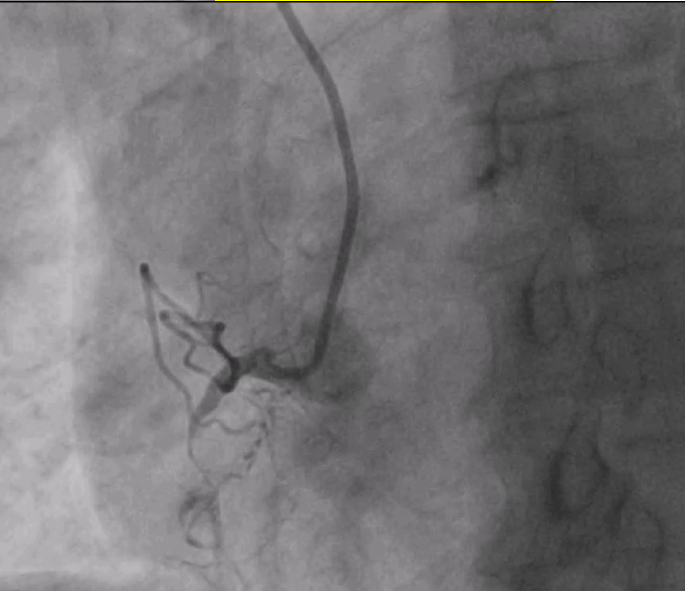

PTCA with Retrograde Rendezvous for Chronic Total Occlusion (CTO)An individual with a stubborn Chronic Total Occlusion (CTO) in the RCA (Right Coronary Artery) initially underwent a failed antegrade percutaneous transluminal coronary angioplasty (PTCA). Despite multiple wire attempts (e.g., CROSSIT 200, PILOT 150), the procedure was aborted due to a spiral dissection.A month later, a second attempt was made using a more advanced approach. The steps were as follows:Retrograde Access: The interventional team chose a retrograde approach, navigating a wire and microcatheter through collateral vessels to reach the RCA distal to the blockage.Antegrade Access: Simultaneously, an antegrade wire was advanced from the proximal end of the RCA to the blockage site.Rendezvous: The retrograde and antegrade wires were "kissed" at the site of the CTO. This crucial step, known as the rendezvous technique, allowed the antegrade wire to be precisely guided.Final Crossing: The antegrade wire was then advanced through the antegrade microcatheter, alongside the retrograde wire, finally penetrating the true lumen distal to the CTO.Revascularisation: Once the path was clear, the retrograde wire was removed. The RCA was then successfully revascularized with balloon dilations and the deployment of two stents.